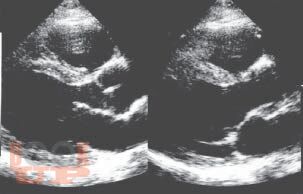

Книга посвящена одному из важнейших разделов детской кардиологии - врожденным порокам сердца. В общей части рассмотрены особенности нормального кровообращения у плода и новорожденного, а также его изменения при врожденной патологии сердца; кроме того, читатель знакомится со специальной терминологией. В разделе частной патологии подробно представлены все основные пороки, встречающиеся в практике детских врачей, алгоритмы их диагностики, современные возможности терапевтического и хирургического лечения; изложены вопросы послеоперационного наблюдения за пациентами. Издание содержит более 140 рисунков и схем, иллюстрирующих ключевые расстройства гемодинамики, методы исследования сердца и наиболее распространенные операции.